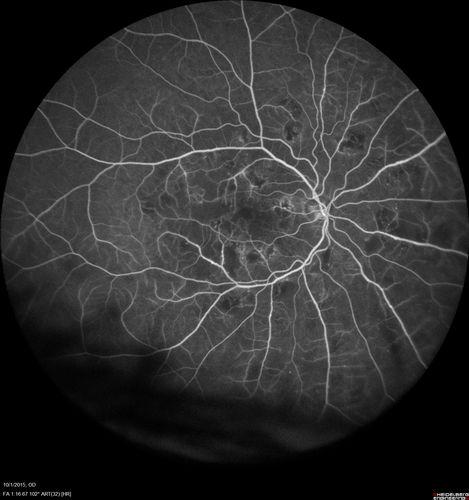

Hairy Cell Leukemia - Retinal Hemorrhage and twig Branch Vein Occlusion

79 year old man He has had hairy cell leukemia since 2002.  He is in remission.  His last blood tests were 9/2018.  He just moved down here and needs a new leukemia doctor.  His vision is fine.

VA OD: Dcc20/25

VA OS: Dcc20/25

IOP: TP: OD:12 OS:12